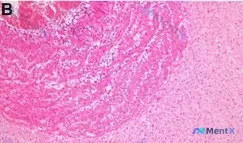

整理到一份挺有讨论/复盘价值的病理读片资料: 标本标注为 (B) 胎盘侧脐静脉,HE 染色 x100 倍。 镜下主要表现: - 背景是粉染均一状/细纤维状的基质,类似淀粉样变或玻璃样变;左上方可见一片深染粉红区,提示出血或富含蛋白的渗出/坏死 - 细胞较小,呈圆形/卵圆形,缺乏显著异型性,排列呈“蜂...